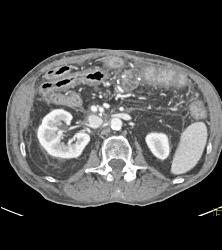

Antral Carcinoma